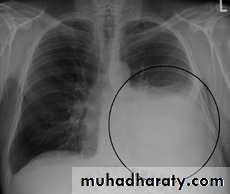

- (CXR) :The classical appearance of pleural fluid on the erect PA chest film is of a curved shadow at the lung base, blunting the costophrenic angle and ascending towards the axilla

Fluid appears to track up the lateral chest wall.

Around 200 mL of fluid is required to be detectable on a PA chest X-ray, but smaller effusions can be identified by ultrasound or CT.

Pleural fluid localised below the lower lobe ('subpulmonary effusion') simulates an elevated hemidiaphragm.

Fluid localised within an oblique fissure may produce a rounded opacity, simulating a tumour.